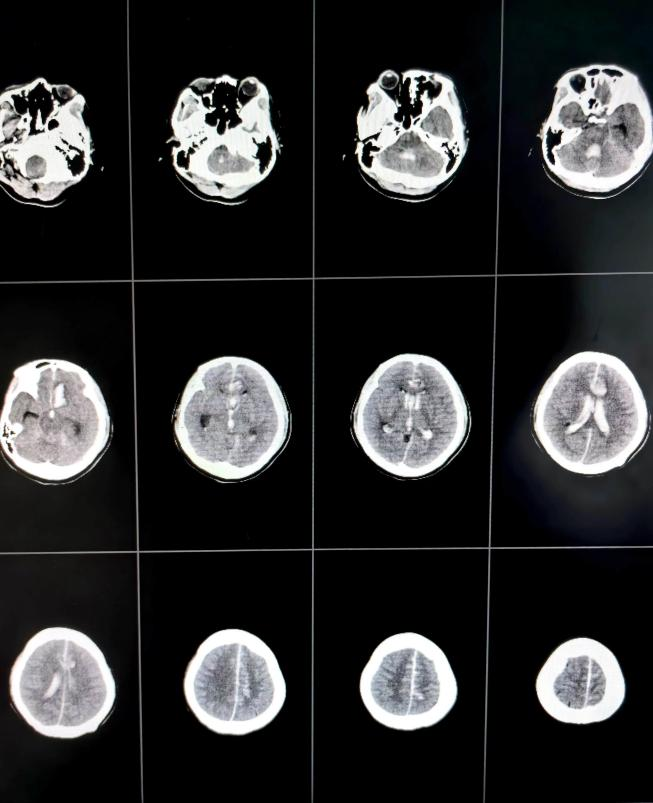

36岁的患者马女士(化名)因“突发意识不清3小时”从临近县医院转入我院,外院CT示蛛网膜下腔出血。来院时,马女士意识已陷入昏迷,频繁恶心呕吐,频发癫痫肢体抽搐。马女士进入急诊医学科后,脑科医院院长纪文军主任医师立即指示开通绿色通道,急诊复查头颅CT示左侧额叶脑出血、脑室积血、蛛网膜下腔出血;脑干受压、密度减低。相比于第一次CT出血明显增多,考虑为颅内动脉瘤二次破裂所致。

术前头颅CT提示颅内血肿、脑室积血、蛛网膜下腔出血

术后第13天头颅CT示颅内出血引流完全,脑室无扩大

由于患者意识昏迷状态,自主呼吸弱,给予气管插管呼吸机辅助呼吸,护理团队给予患者特级护理,进一步引流颅内积血及血性脑脊液,术后第3天再给患者行腰大池引流术。在神经外科二病区医护团队的精心治疗护理下,患者术后第6天顺利脱呼吸机,术后第13天完全清醒,肢体肌力逐渐恢复正常。现患者意识清楚,四肢无明显偏瘫等神经功能障碍,现已康复出院。